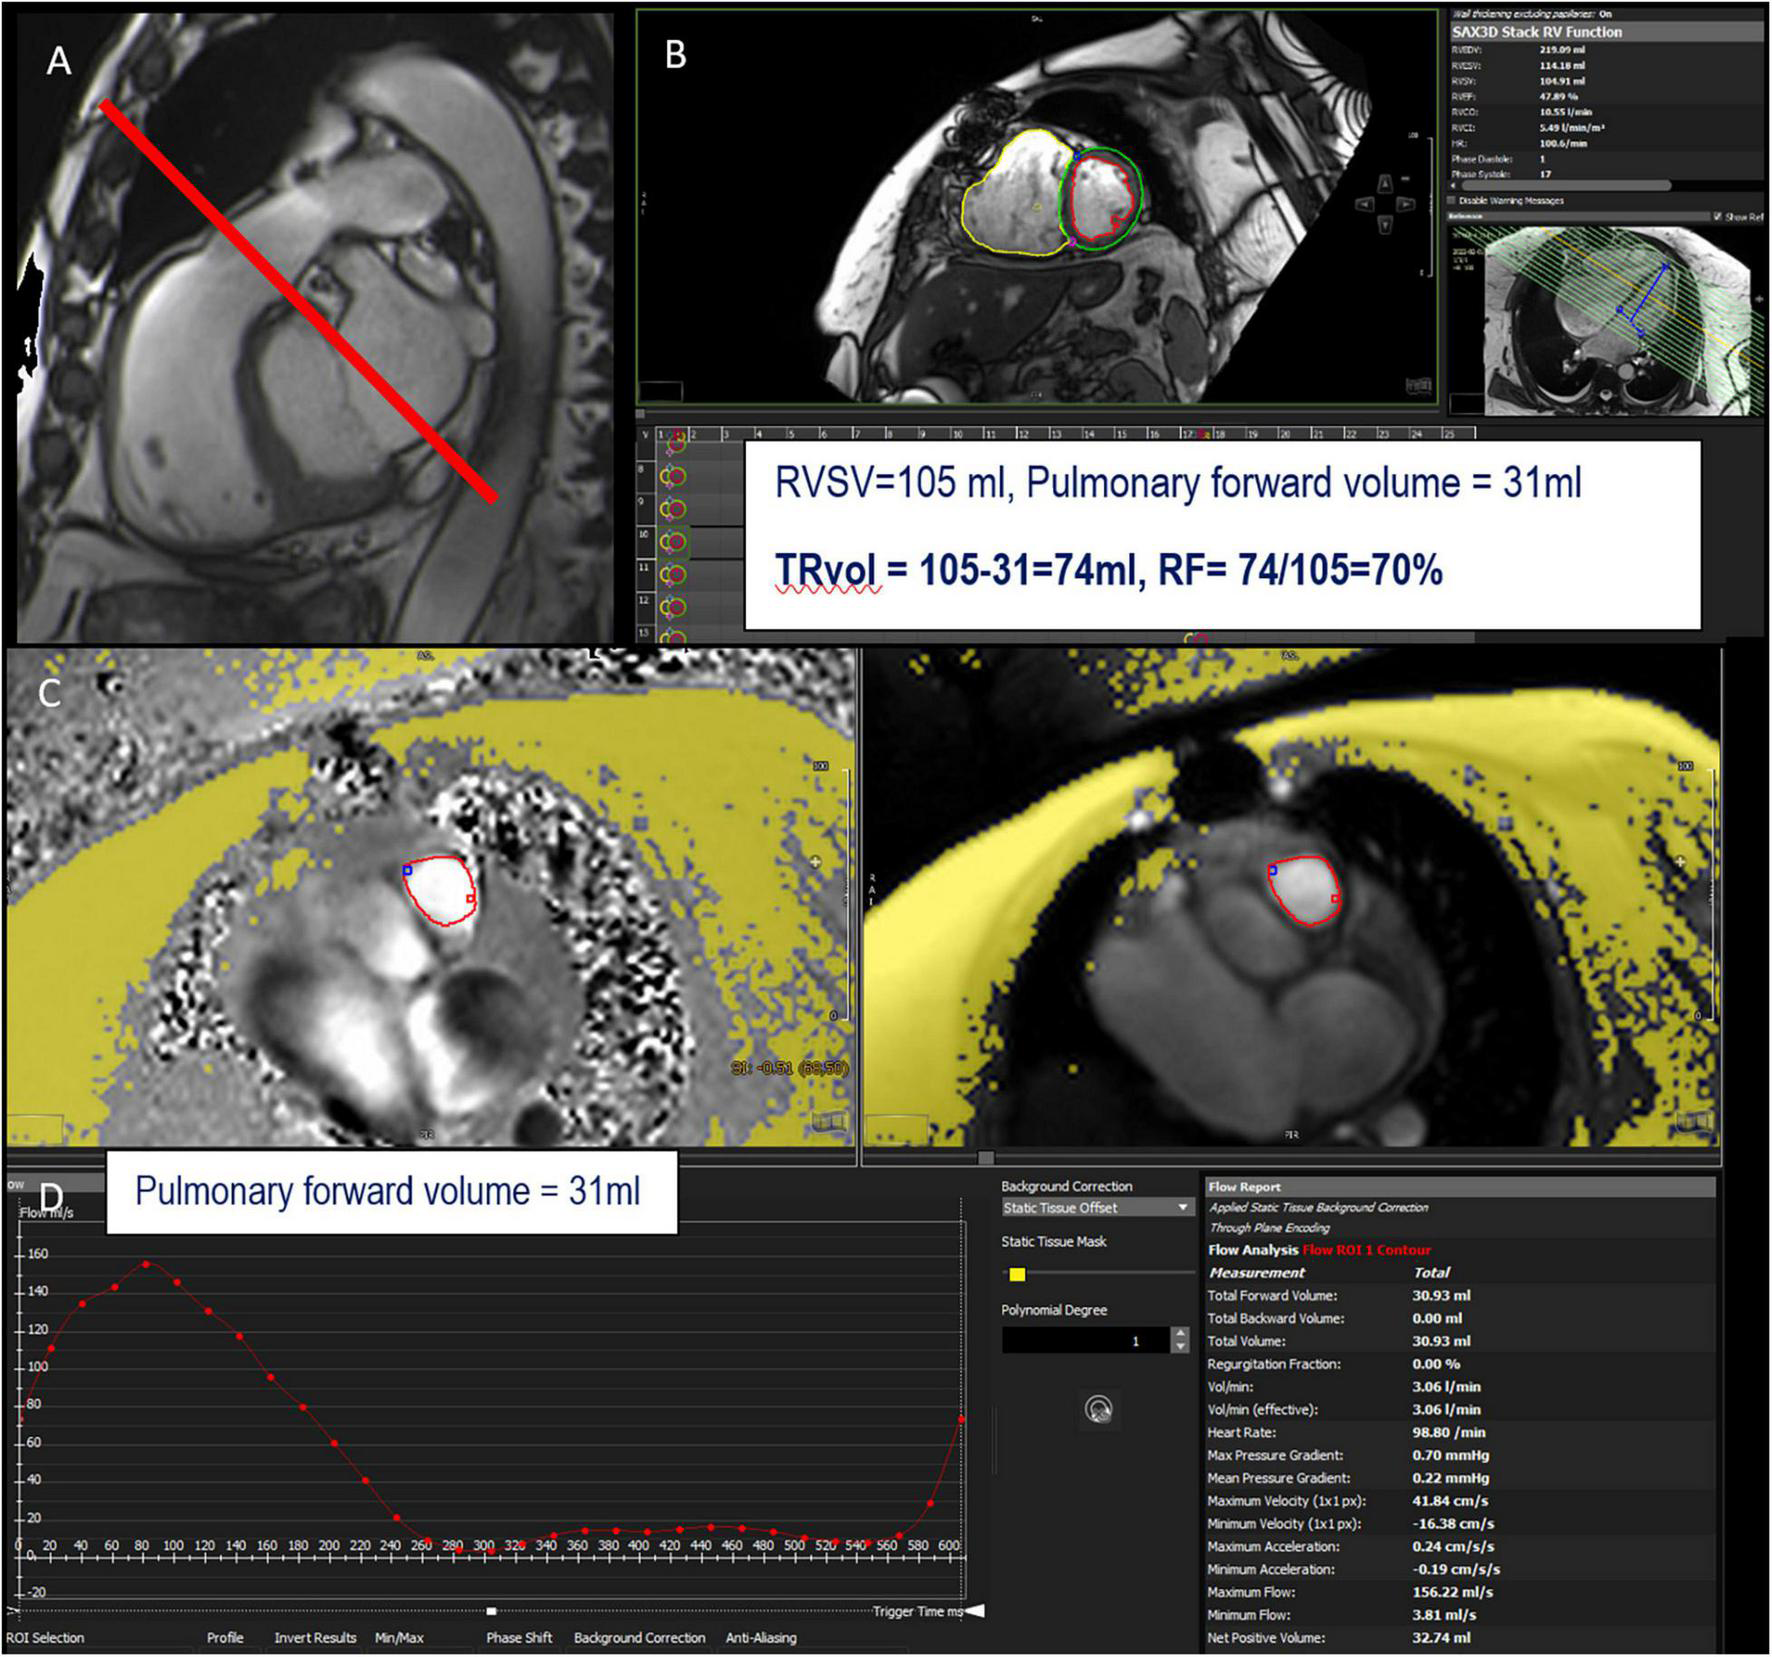

Similar to MR, the regurgitant volume of TR (TRvol) can be measured indirectly as the difference between RVSV and PFF (or AFF in the absence of AR) using 2D cine (for RVSV) and retrospective acquisition with velocity-encoded phase-contrast sequence in a through–plane on the pulmonary valve (or the aortic valve), 5 mm above the valve (12) (Figure 7).

FIGURE 7

Example of TR assessment using indirect method n°1. RVOT bSSFP images showing slice position in the pulmonary artery (red line) for phase-contrast velocity mapping to obtain pulmonary forward volume (A). Assessment of right ventricular stroke volume (RVSV) from short-axis cine SSFP images (B). Phase and magnitude images with delineation of the pulmonary artery (C) allowing flow curves (D). This patient has a severe TR with a tricuspid regurgitant volume (TRvol) of 74 ml and a regurgitant fraction (RF) of 70%.